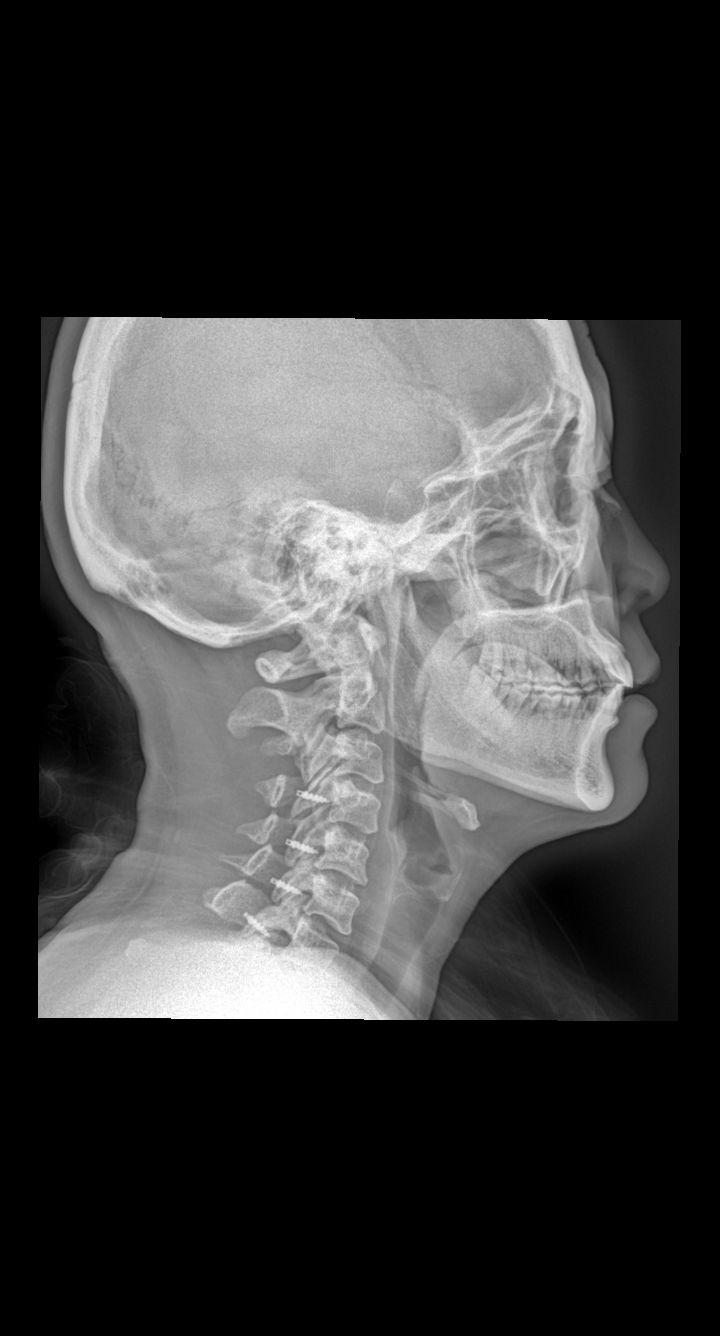

颈椎术后,疼痛就诊 45岁